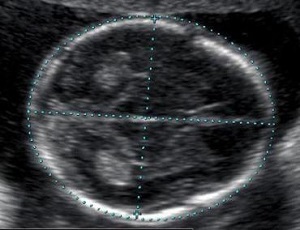

УЗИ на 16 неделе беременности

На 16–18 неделе врач назначает второй пренатальный ультразвуковой скрининг. Снимки плода на этом сроке беременности выглядят следующим образом:

Ультразвуковое исследование на 16 неделе беременности

Обычно исследование занимает 15–45 минут. Оно помогает решить важные задачи:

Показатели плода, которые может оценить врач во время второго планового ультразвукового исследования:

1 – лобно-затылочный размер. 2 – бипариетальный размер. |

Бипариетальный размер – поперечный размер головки плода, измеряется между выступающими частями теменных костей (находятся выше височных костей). Размеры в норме, в зависимости от срока беременности: · 16 недель – 3,4 см. · 17 недель – 3,8 см. · 18 недель – 4,3 см. · 19 недель – 4,7 см. · 20 недель – 5 см. · 21 неделя – 5,3 см. · 22 недели – 5,7 см. |

Лобно-затылочный размер – продольный размер головки, измеряется между выступающими частями лобной и затылочной кости. Размеры в норме, в зависимости от срока беременности: · 16 недель – 4,5 см. · 17 недель – 5 см. · 18 недель – 5,3 см. · 19 недель – 5,7 см. · 20 недель – 6,2 см. · 21 неделя – 6,5 см. · 22 недели – 6,9 см. |

Цефалический индекс – показатель, который помогает оценить форму головки плода. Для того чтобы его рассчитать, нужно разделить бипариетальный размер на лобно-затылочный. Цефалический индекс выражается в процентах. Возможные показатели: · 71–85% — мезоцефалическая форма черепа, можно считать нормой, средним значением, встречается у большинства людей. · Более 85% — брахицефалическая форма черепа (короткий и широкий череп). · Менее 71% — долихоцефалическая форма черепа (узкий и длинный череп). |

Окружность головки плода: · 16 недель – 12,4 см. · 17 недель – 13,5 см. · 18 недель – 14,6 см. · 19 недель – 15,8 см. · 20 недель – 17 см. · 21 неделя – 18,3 см. · 22 недели – 19,5 см. Если получился показатель выше или ниже указанных значений, это еще не повод бить тревогу, так как отклонение может быть вариантом нормы. Иногда оно свидетельствует о гидроцефалии и других патологиях. |

Окружность живота – показатель, который помогает оценить рост и развитие плода: · 16 недель – 10,2 см. · 17 недель – 11,2 см. · 18 недель – 12,4 см. · 19 недель – 13,4 см. · 20 недель – 14,4 см. · 21 неделя – 15,7 см. · 22 недели – 16,9 см. |

Длина плечевой кости: · 16 недель – 2,1 см. · 17 недель – 2,3 см. · 18 недель – 2,7 см. · 19 недель – 3 см. · 20 недель – 3,3 см. · 21 неделя – 3,5 см. · 22 недели – 3,6 см. |

Длина бедренной кости: · 16 недель – 2,1 см. · 17 недель – 2,5 см. · 18 недель – 3 см. · 19 недель – 3,3 см. · 20 недель – 3,5 см. · 21 неделя – 3,7 см. · 22 недели – 4 см. |